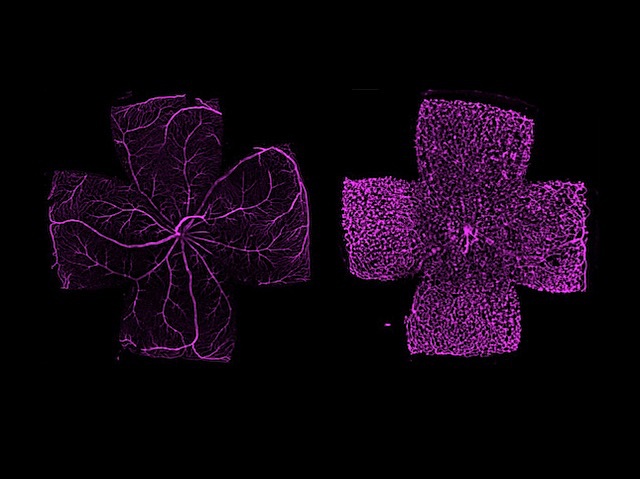

Your retinas — the light-sensitive tissue at the backs of your eyes — are nourished by an extensive network of blood vessels. Any disruption to this blood flow can spell trouble for your vision. Abnormal blood vessels are a feature of many eye diseases. Modelling these vascular changes is key to uncovering new therapeutic targets. TGF-β is a signalling molecule involved in blood vessel development, and here researchers have created a mouse model without TGF-β in their retinal vessels. Highlighting blood vessels under fluorescence microscopy revealed the difference between retinas lacking TGF-β (pictured, right) and normal retinas (left). The defects are characteristic of those occurring in retinal diseases such as knot-like new blood vessels called vascular tufts (right) found in diabetic retinopathy.